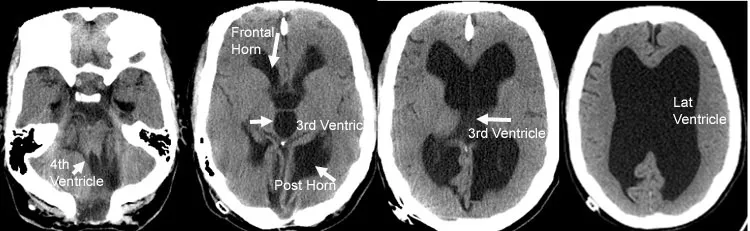

- Hydrocephalus: ↑ CSF volume → ventricular dilation ± ↑ Intracranial Pressure (ICP).

- Communicating (Non-obstructive): Impaired CSF reabsorption by arachnoid granulations (e.g., post-meningitis, subarachnoid hemorrhage). Ventricles are symmetrically dilated.

- Non-communicating (Obstructive): Blockage within the ventricular system (e.g., aqueductal stenosis, tumor). Dilation occurs proximal to the obstruction.

- Normal Pressure Hydrocephalus (NPH): Chronic communicating hydrocephalus in the elderly.